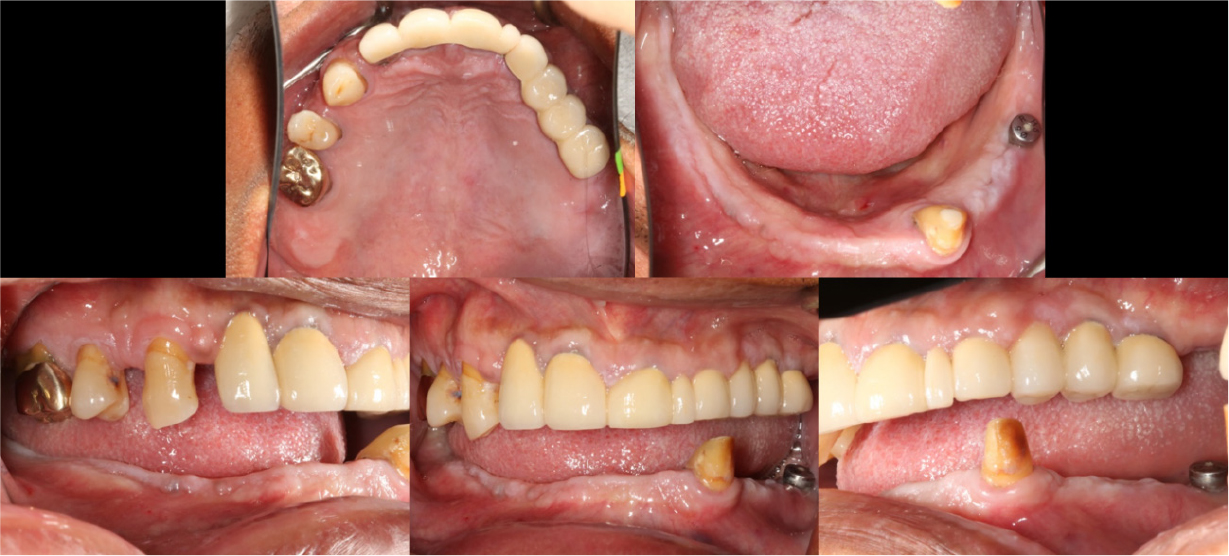

A 58-year-old male patient visited our hospital with chief complaints of missing mandibular teeth. The patient had hypertension and hyperlipidemia. Clinical and radiological examinations revealed multiple tooth loss in the mandible and canting of the maxillary teeth. The implant in the lower left second premolar area showed degree II mobility and vertical bone loss around the fixture, indicating a loss of osseointegration (Figs. 1 and 2). After removal of the dental implant on #35, implant placement was planned at sites #47, 46, 44, 43, 32, 33, 34, 36, and 37. The patient refused to undergo temporary denture placement. A radiographic stent was fabricated after bite registration using a record base, which is the conventional method for fabricating a stent in a partially edentulous jaw. CBCT was taken, and the stone model was scanned using an optical scanner (Medit T500 Dental 3D Scanner; Medit Corp., Seoul, Korea) (Fig. 3A).

Provisional fixed implant prostheses were placed after the healing period (Fig. 8). The final prostheses were planned to be completed after verifying the vertical dimensions and occlusion using the provisional prostheses.